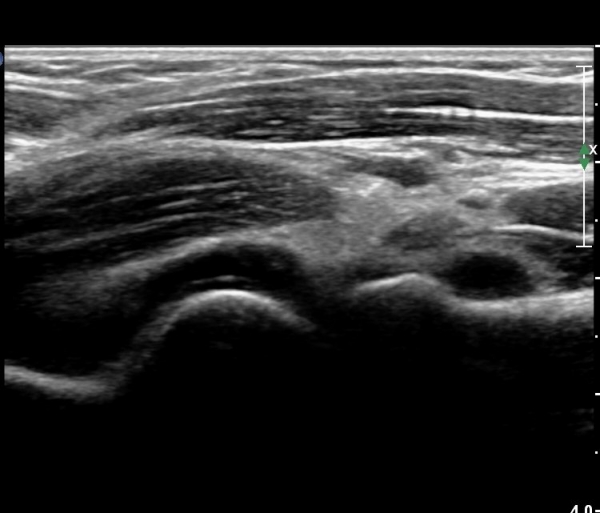

ÆÈ²ÞÄ¡ µÚÂÊ Á¾´Ü¸é°Ë»ç¿Í Ⱦ´Ü¸é°Ë»ç¿¡¼­ ÁֵοÍ(olecranon fossa)¿¡ ¼ö¾×Àú·ù°¡ °üÂûµÊ(»çÁø 1, 2)